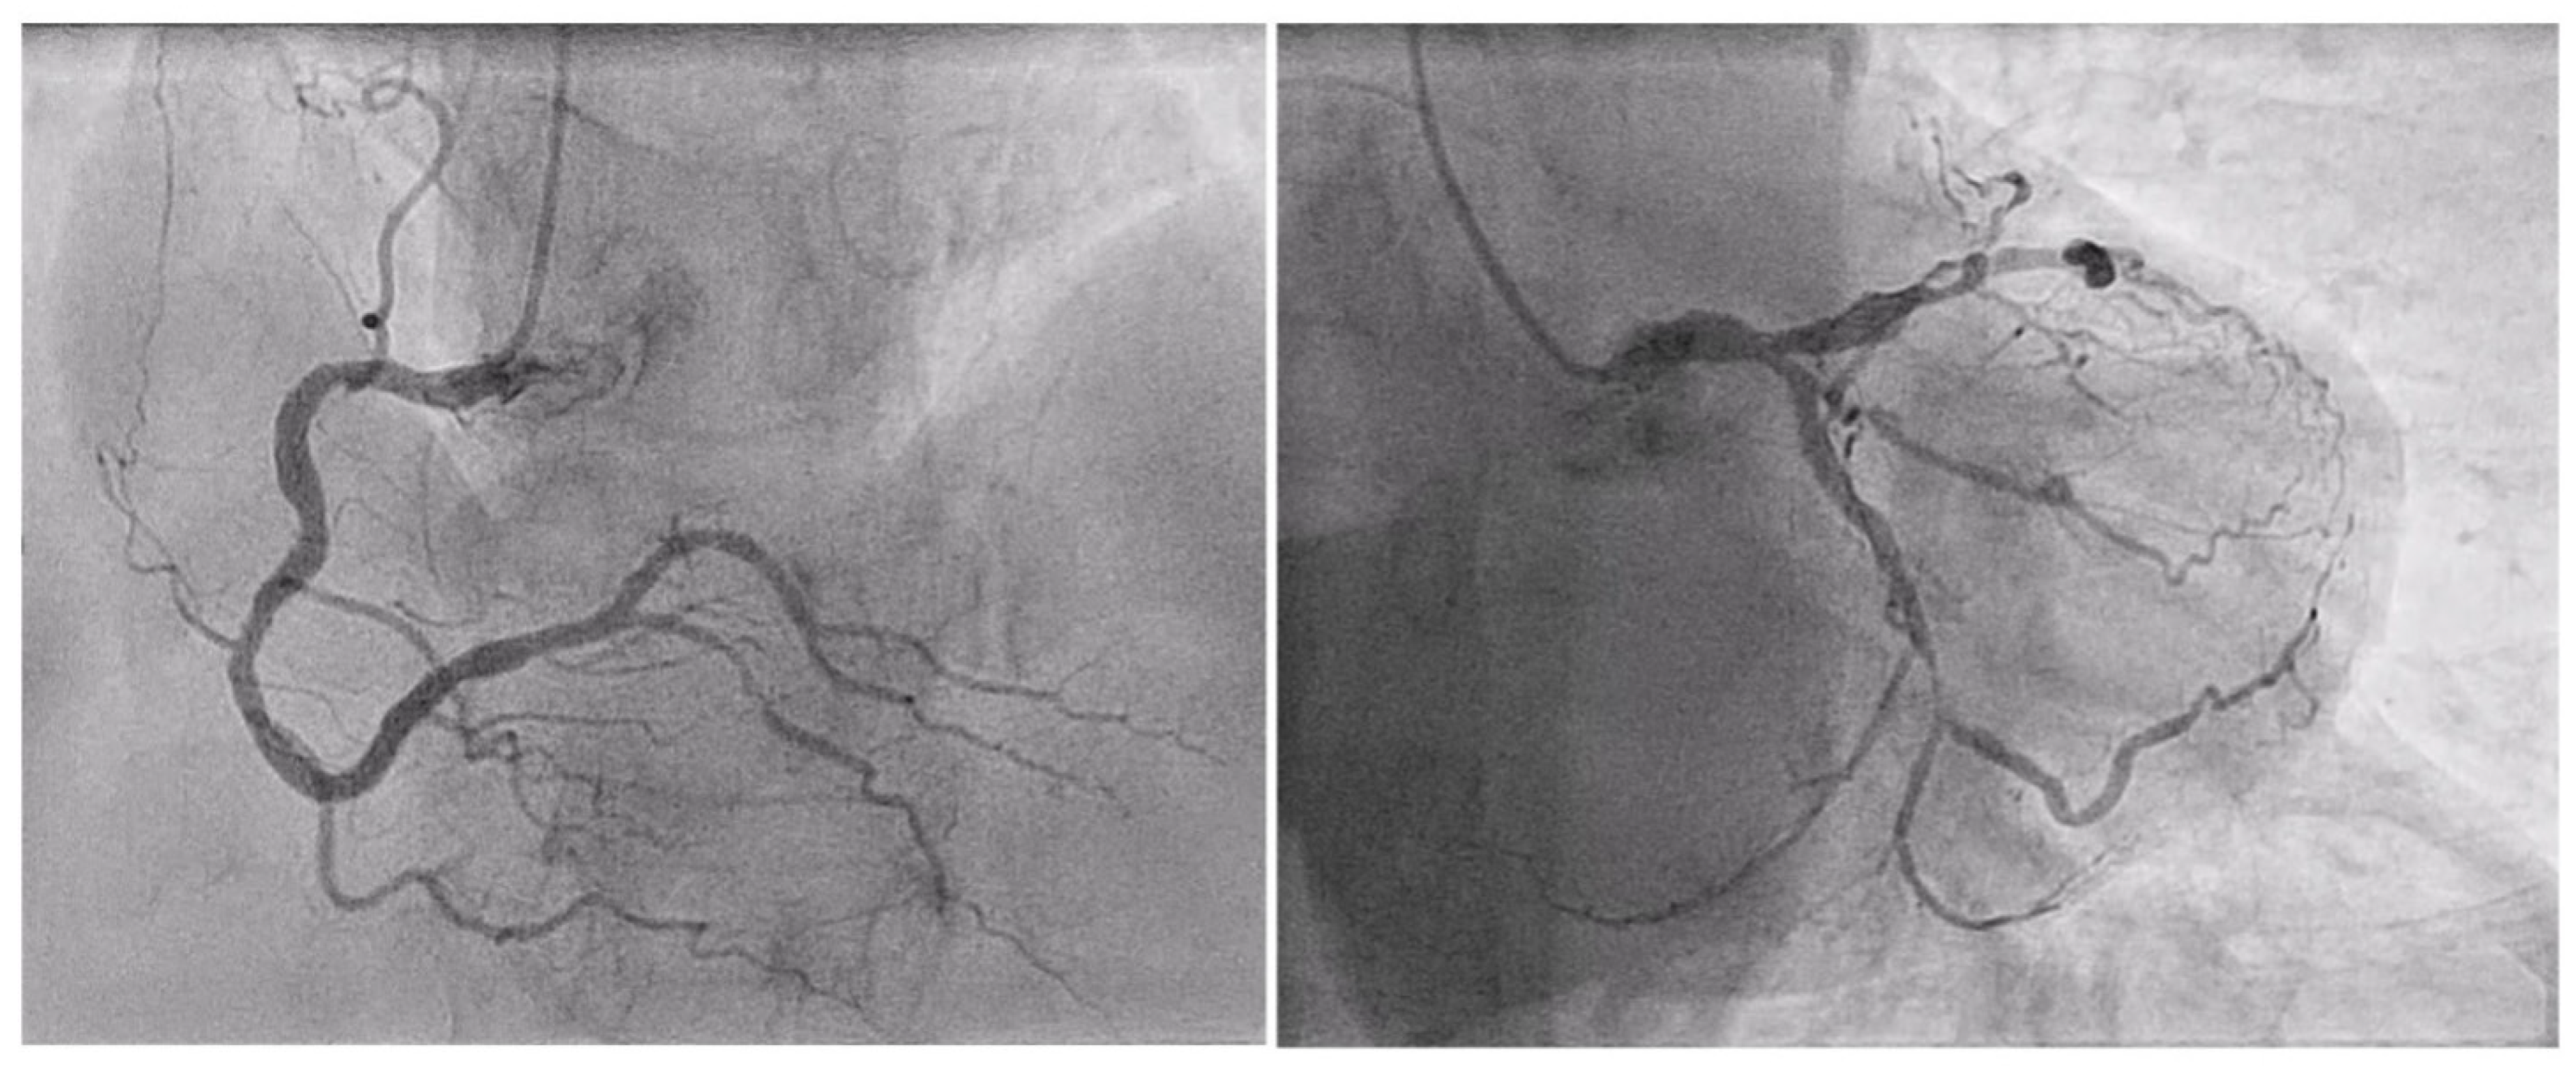

| LIMA angiographic patency at staged PCI (n° of pts, %) | 10 (100%) |